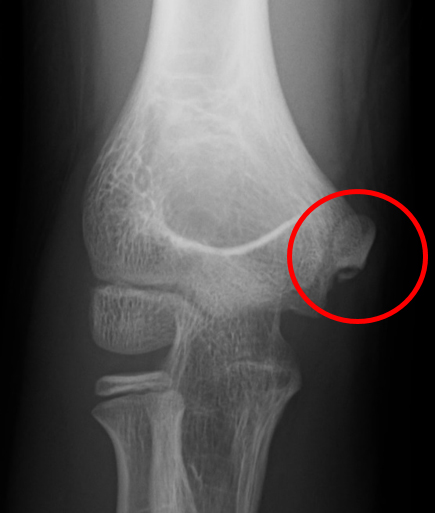

内側上顆下端裂離骨折は、肘の靭帯が付着する骨が投球動作により牽引されて剥がれる怪我です(図9)。小学生に多い怪我で痛みが引けば投球再開・競技復帰が可能となります。しかし、近年、この骨折の後遺障害で骨が変形したり、癒合が得られないことで、高校生以上に内側側副靭帯損傷を発症する選手が多いことが分かってきました(図10)。当院では、「骨をきちんと癒合させる」ことにこだわっており、簡易型プラスチック装具(図11)で一定期間固定を行っております。後遺障害を起こさないよう治癒させることを目指しています。

当院の調査では、内側上顆に学童期の遺残裂離骨片を有する症例(図2:リスク2.6倍),MRIでの完全損傷(図3:リスク4.6倍)を有する症例が手術を要するリスクが高まることが分かっています。詳細な評価に基づく診断を行い,3ヶ月以上のリハビリテーションを主体とした保存療法を行っても競技復帰が達成できない場合は手術療法を考慮します。手術を行う条件として,選手が競技復帰・継続を強く希望することが必須となります。